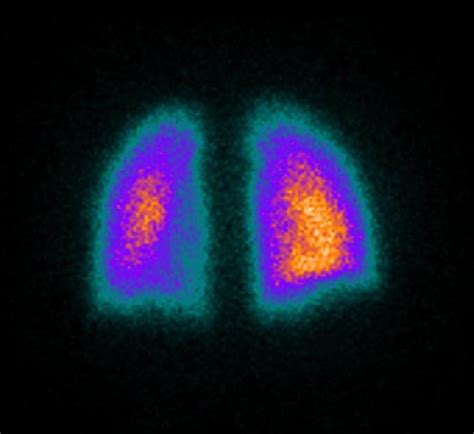

Nuclear Medicine Lung Perfusion Scan Nuclear Scans: MedlinePlus

Learn what to expect during a Ventilation Perfusion Scan. This diagnostic imaging test evaluates lung function by measuring airflow and blood flow. Discover how this nuclear medicine procedure helps doctors detect pulmonary embolisms, assess breathing issues, and identify underlying respiratory conditions to ensure an accurate diagnosis and effective treatment plan for your lung health.